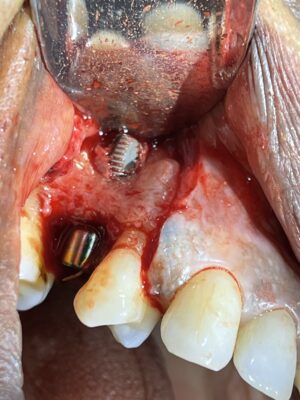

Jonnathan posted an update a year ago

I have been placing Implant club implants for the past 2-3 years (yes Ivan, I know you that much), and my beautiful GF needed an implant. Extraction and bone grafting was performed. Today I did the uncover. 60% of my cases, I have notice this overgrowth of bone. This on was part of the statistics. I just wanted to show off/share the case.

She…

Brother, this is looking beautiful man!! Nice work, Yes, I noticed that we get really nice bone levels too 🙂

Placing an Implant Club implant on your girlfriend is the equivalent of getting an Implant Club tattoo on your forehead! Thank you for your trust my friend!